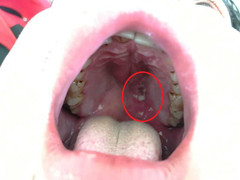

Có rất nhiều bệnh nguy hiểm có biểu hiện đầu tiên qua miệng mà chúng ta không biết, đến khi phát hiện thì có thể bệnh đã trở nặng, gây ảnh hưởng nghiêm trọng đến sức khỏe.

(VTC News) - Một người đàn ông ung thư miệng ở Đài Loan bị nhà hàng đuổi ra ngoài khi ông cùng cả gia đình đến liên hoan.